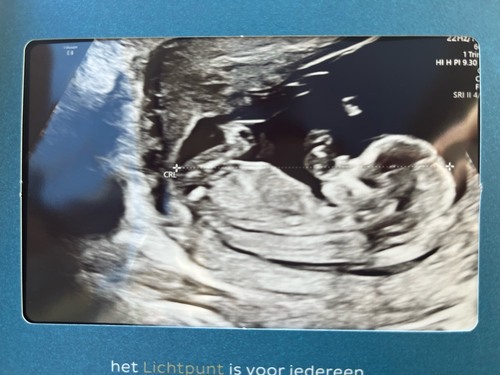

Ik zie alleen een hele overduidelijke nub goed hoor dus bestudeer ze niet zo lang en goed met bewerken enzo als nubster🤭

Wat ik wel doe is dat ik kijk naar nub én skull theorie. Daarmee samen kom ik bij jou uit op een meisje💗

Je laatste foto is dan weer wat verwarrend, maar dat kan ook de navelstreng zijn aangezien we de hoek niet goed kunnen zien waarin de foto genomen is🙃

Ik ga toch voor 💙